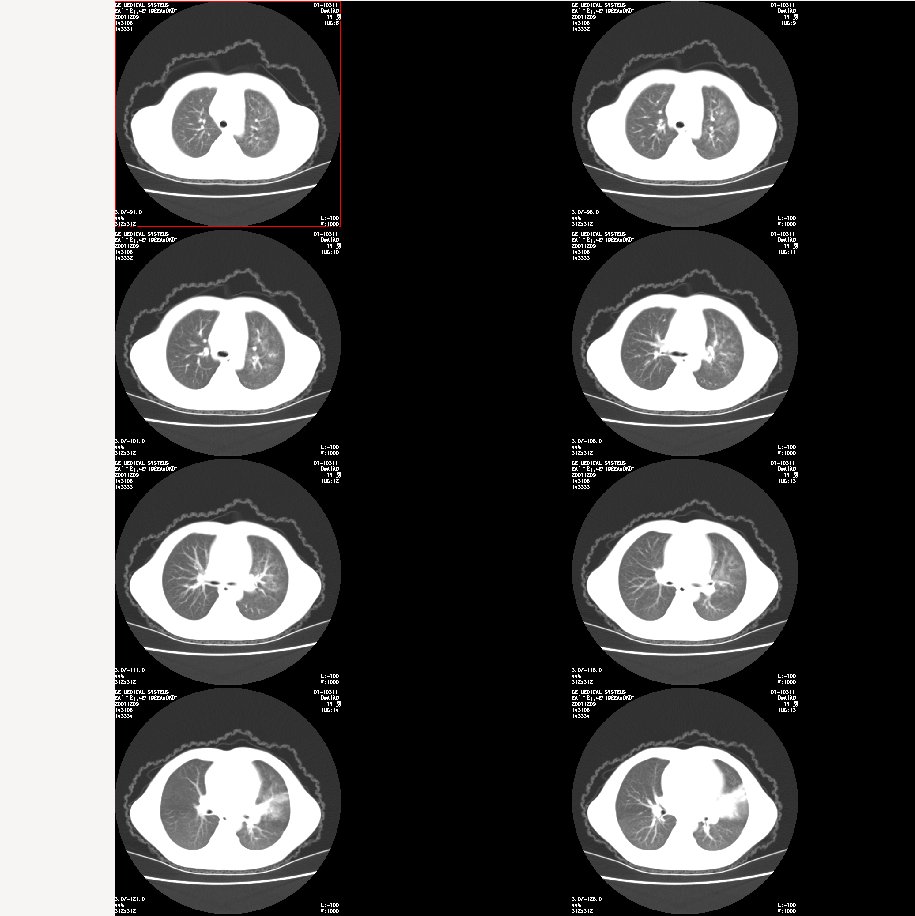

m 7

咳嗽、咯血半月。查体:双肺呼吸音粗,可及干湿鸣。自诉每年均有发作。

肺窗:

图像太小了,不好看,左肺出血、感染性病变?

双肺感染性病变——结核可能性大!

炎症应该有,排除一下有没有支扩吧

左肺上叶上舌段不张实变,建议纤支镜检查

支持 肺发育不全伴感染与支气管扩张